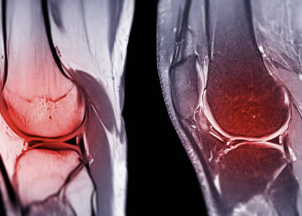

무릎 십자인대 파열 증상 및 십자인대 파열에 대해 알아보는 시간 갖도록 하겠습니다.

십자인대는 무릎 관절 내부에 있는 4개의 인대 중 하나로, 대퇴골과 승골 사이에 위치해 있습니다. 십자인대는 무릎 관절의 안정성을 유지하는 역할을 담당합니다. 무릎 관절에 직접적인 충격이 가해지거나, 무릎이 강한 스트레스를 받았을 때 십자인대가 손상되는 경우가 있습니다. 이러한 십자인대 손상은 스포츠 활동이나 사고 등으로 발생할 수 있습니다. 십자인대 손상 증상으로는 무릎 통증, 부종, 불안정감 등이 있으며, 심한 손상의 경우 수술이 필요할 수도 있습니다. 십자인대 손상을 예방하기 위해서는 적절한 스포츠화를 착용하고, 몸을 충분히 기르며, 스포츠를 할 때 안전장비를 착용하는 것이 중요합니다.

무릎 십자인대 파열은 무릎 관절 내부에 있는 십자인대 중 하나가 부분적으로 또는 완전히 파열되는 상황을 말합니다. 무릎 십자인대 파열 증상은 다양합니다. 주요 증상은 다음과 같습니다.